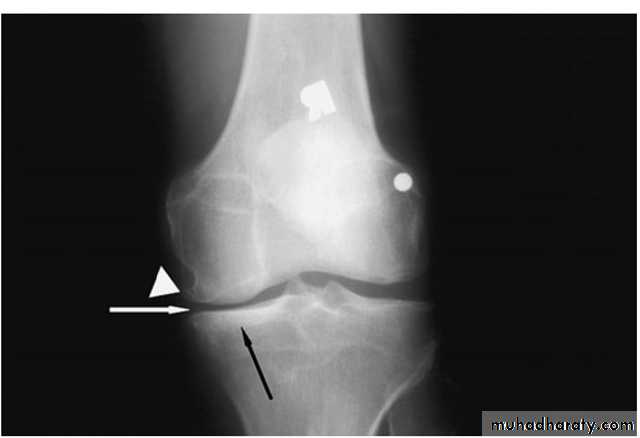

Osteochondritis dissecans of the medial femoral condyle

Osteochondritis dissecans of the medial part of the articularsurface

Osteochondritis dissecans :

affects the large articular surface , commomnly medial femural condylee ,talus and trochlea .

Ends by separation of the affected part in to the joint space resulting in intra-articular loose body .